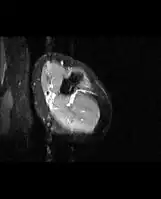

Medical imaging usually shows a well-defined wide-based bony growth on the surface of bone.[5] It can be pedunculated and irregular, giving it a "bizarre" appearance, and is not connected to underlying bone.[2]

MRI mid-upper arm

MRI mid-arm axial view